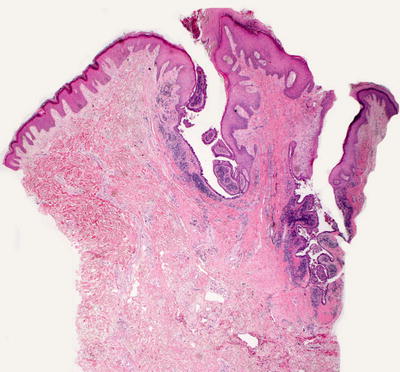

Fig. 24.2

Pilomatricoma demonstrates a sharply circumscribed dermal tumor consisting of basaloid cells at the periphery, ghost cells and a keratinaceous center